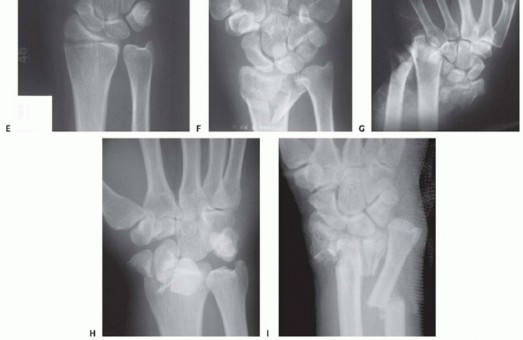

FIG 4 • A. Positioning for standard lateral radiography. B. Standard lateral radiograph. C. Positioning for 10-degree lateral radiography. D. Ten-degree lateral radiograph. Note the improved visualization of the articular surface of the base of the scaphoid facet and the entire lunate facet. Injuries from a high-energy mechanism present as complex comminuted fractures of the articular surface with extension into the radial/ulnar shaft ( FIG 3I).